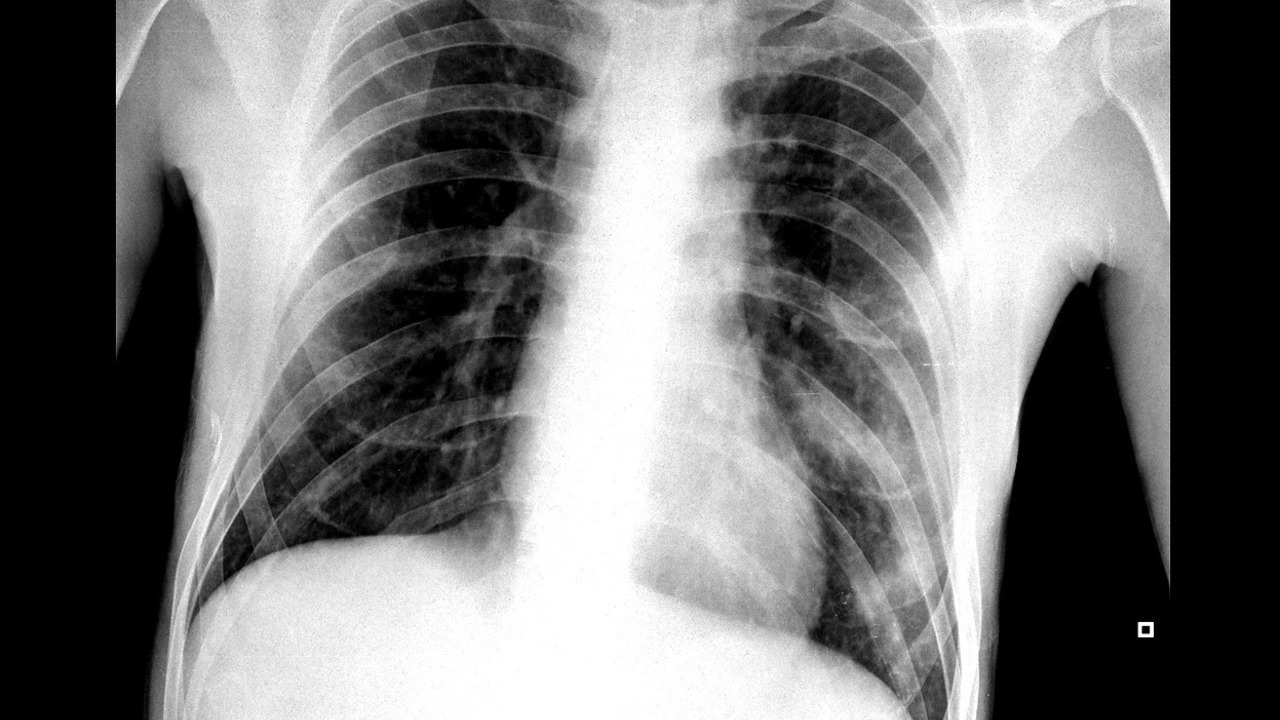

De manera general la radiación afecta a todo el mundo por igual, sin embargo, hay franjas de edad con más riesgo que otras. Por ejemplo, diferentes investigaciones apuntan a que la exposición a radiaciones ionizantes es más peligrosa en los menores de 30 años.

El principal motivo no es otro que por prevención en la consecuencia de esas radiaciones. Estas pueden generar un cáncer, y los mayores de 30 años tienen más probabilidad de no aguantar ese sufrimiento durante más de dos o tres décadas. Es por eso que se intenta evitar a los más jóvenes.